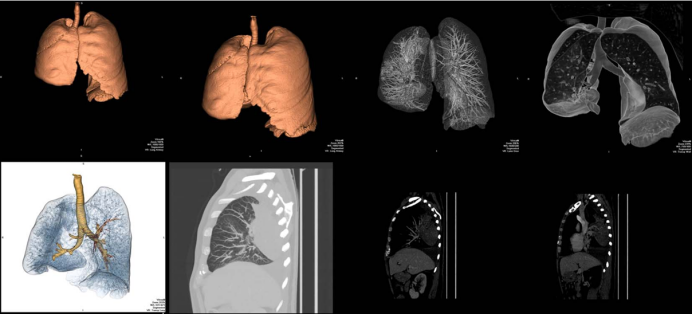

这“翻转”来的太突然,即使再次胸片检查也依旧如此。不得已行CT检查和三维渲染重建,见图3。胸部CT示右侧斜裂反转,中间支气管异常前行,肺血管旋转;右下肺动脉与中间支气管一起被拉向前行;右肺广泛实变,并伴有胸腔积液;外观显示右肺发生了180度扭转。

图3 胸部CT